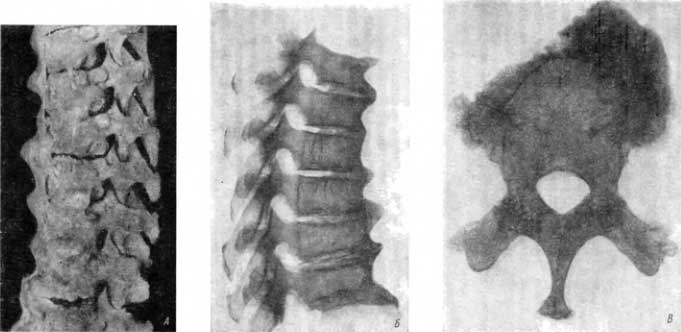

Позвоночный столб с IV шейного и по XII грудной позвонок был резко деформирован в результате обширного и мощного окостенения передней продольной связки и уплощения тел некоторых позвонков (рис. 114, А).

Рис. 114. А — тяжелый деформирующий спондилоз, исключавший возможность движений на всем протяжении поражения; Б — окостеневшая передняя продольная связка сковала 6 грудных позвонков в одно костное образование; В — огромные костные разрастания на теле IX грудного позвонка; проявления деформирующего артроза на поперечных отростках.

Шесть грудных позвонков — с III по VIII — были спаяны в единое костное образование благодаря сплошному окостенению передней продольной связки. На передней поверхности этого отдела позвоночника места перехода тела одного позвонка в другой отличаются резкими выступами (рис. 114, А, Б). В боковых отделах, где нет окостеневшей передней продольной связки, прослеживаются несколько сниженные в высоту межпозвоночные пространства.

Эти особенности при наличии неизмененных межпозвонковых суставов позволяют с уверенностью поставить диагноз медленно развивавшегося дегенеративно-дистрофического поражения, а именно тяжелого деформирующего спондилоза с поздним вторичным анкилозированием тел указанного отдела позвоночника (от III до VIII грудного), и исключить инфекционно-воспалительный анкилозирующий спондилоартрит (болезнь Бехтерева).

Дегенеративно-дистрофическое поражение позвоночника не ограничивается указанными позвонками. Огромные костные разрастания такого же порядка имеются в области IX грудного позвонка (рис. 114, В). Они резче выступают справа, чем слева; новообразованный костный выступ справа по размерам почти равен телу этого позвонка. Эта окостеневшая масса, однако, не привела к спайке с ниже и выше расположенными телами позвонков.

Тела X и XI грудных позвонков спаяны между собой в единое целое окостеневшей передней продольной связкой.

На теле XII грудного позвонка имеется почти такое же обширное, клювовидное костеобразование, как на теле IX грудного позвонка, — тяжелая форма деформирующего спондилоза.